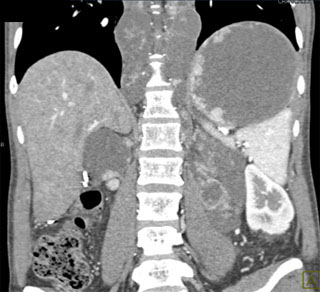

The best diagnosis in this case is?

lymphoma

germ cell tumor

metastatic renal cell carcinoma

disseminated TB